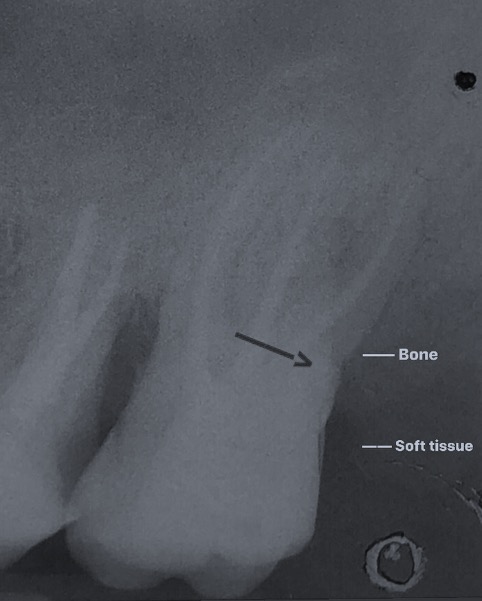

Una corretta terapia canalare con un perfetto sigillo a livello degli apici delle radici è fondamentale. I denti devitalizzati impropriamente possono creare ulteriori problemi che poi andranno a ripercuotersi sulle cure effettuate successivamente come le ricostruzioni e le corone protesiche con conseguente fallimento del piano terapeutico.

Capita spesso di incontrare denti già devitalizzati in maniera impropria che necessitano, seppur asintomatici, di essere ritrattati per evitare che i granulomi infetti visibili radiograficamente si evolvano riassorbendo tutto l’osso sottostante.